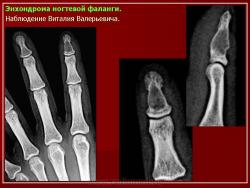

Энхондрома (син.: хондрома, центральная хондрома) — доброкачественная хрящевая опухоль, расположенная в костномозговом канале (интрамедуллярно). Встречается в 10 % случаев от общего числа доброкачественных опухолей костей. Считается, что она возникает из эктопически расположенных островков хряща, отщепившегося от пластинки роста на ранних этапах онтогенеза. В ряде случаев опухоль остается бессимптомной и обнаруживается случайно при рентгенологическом исследовании. В других случаях возникают боль и припухлость. Обычно болезненными становятся все энхондромы фаланг. Наиболее частая локализация: фаланги, главным образом, пальцев кистей, проксимальный конец плечевой кости, проксимальный или дистальный концы бедренной кости. При рентгенологическом исследовании в энхондроме определяются просветления с участками минерализации. Тень кости становится более широкой, кортикальный слой сохраняет целостность, но истончается. В редких случаях энхондрома имеет вид эксцентрически растущего экзофитного новообразования. Макроскопически опухоль представляет собой голубовато-белую полупрозрачную хрящевую ткань, в которую вкраплены желтоватые участки обызвествления. Опухоль состоит из отдельных хрящевых узелков, диаметр которых варьирует в пределах 1 см.

Рентгенологическая картина хондромы представляет четко очерченный опухолевый узел. Очаги минерализации в хондромах выглядят достаточно характерно и представлены очаговыми, глыбчатыми или кольцевидными , арочными отложениями извести. Полного разрушения кортикального слоя трубчатой кости с выходом опухолевых масс в мягкие ткани не наблюдается.

Энхондрома.